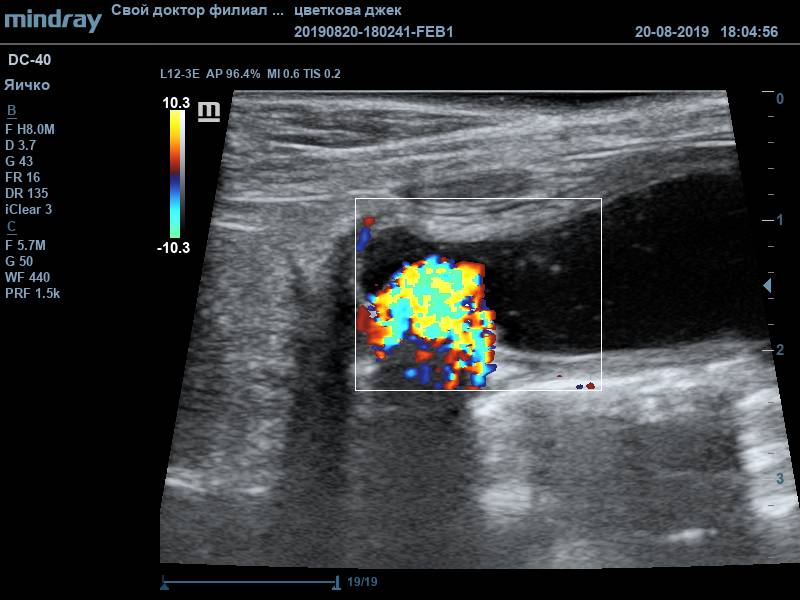

Во время УЗ-диагностики были обнаружены следующие изменения: неравномерное утолщение стенки мочевого пузыря (от 0,3 до 0,7см), слизистый слой гиперэхогенный. В содержимом мочевого пузыря присутствовал обильный крупнодисперсный осадок. В области мочевого треугольника визуализировалось пристеночное рыхлое ассиметричное образование с признаками васкуляризации, размер образования 1,27*0,75см. По заключению данного исследования дифференциальным диагнозом стало новообразование мочевого пузыря, в т.ч. злокачественное. Подобный диагноз окончательно ставится только по результату гистологического исследования материала. Получение материла для проведения анализа возможно в подобных ситуациях только посредством травматической катетеризации или открытой биопсией. Если подтверждается наличие злокачественной опухоли, то в таком случае разрабатываются план хирургического лечения (если оно возможно) и схема курсов химиотерапии.